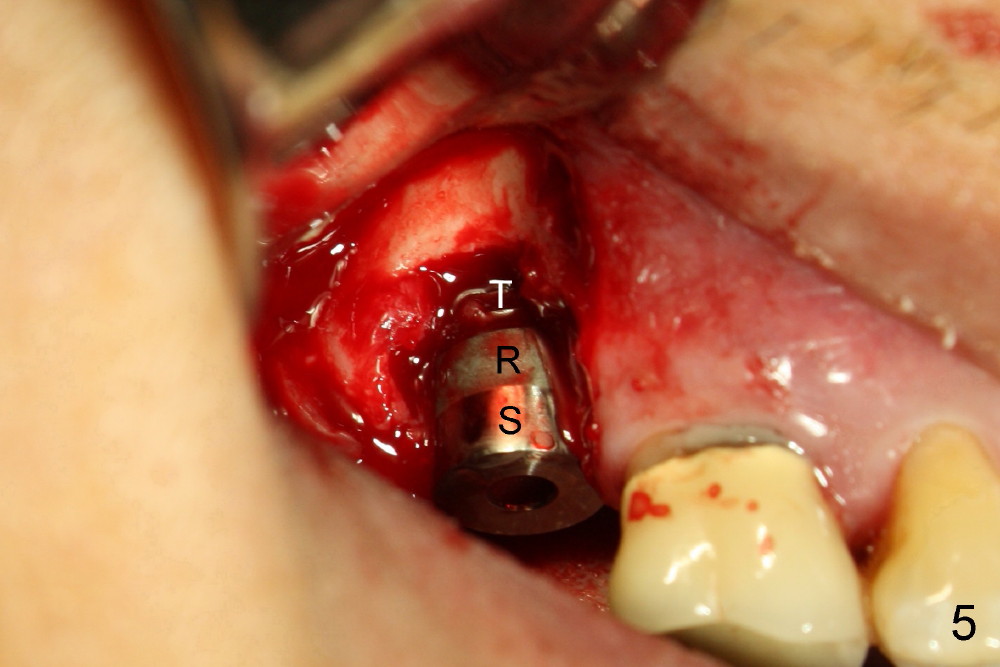

The implant threads (T) are exposed buccally. A flap is raised (Fig.5) with periosteum underscored. After placement of Osteogen (HA 300-500 µm) and Collaform (a collagen membrane, Fig.6*), the flap is sutured. There is no intra- or post-op nasal hemorrhage. The wound heals (Fig.7 (5 days postop), 8 (18 days)). It is apparent that the membrane (Fig.7 *) is replaced by the healing gingiva (Fig.8 *). Three months postop, the buccal gingiva looks normal (Fig.9) around the stable implant (Fig.10).